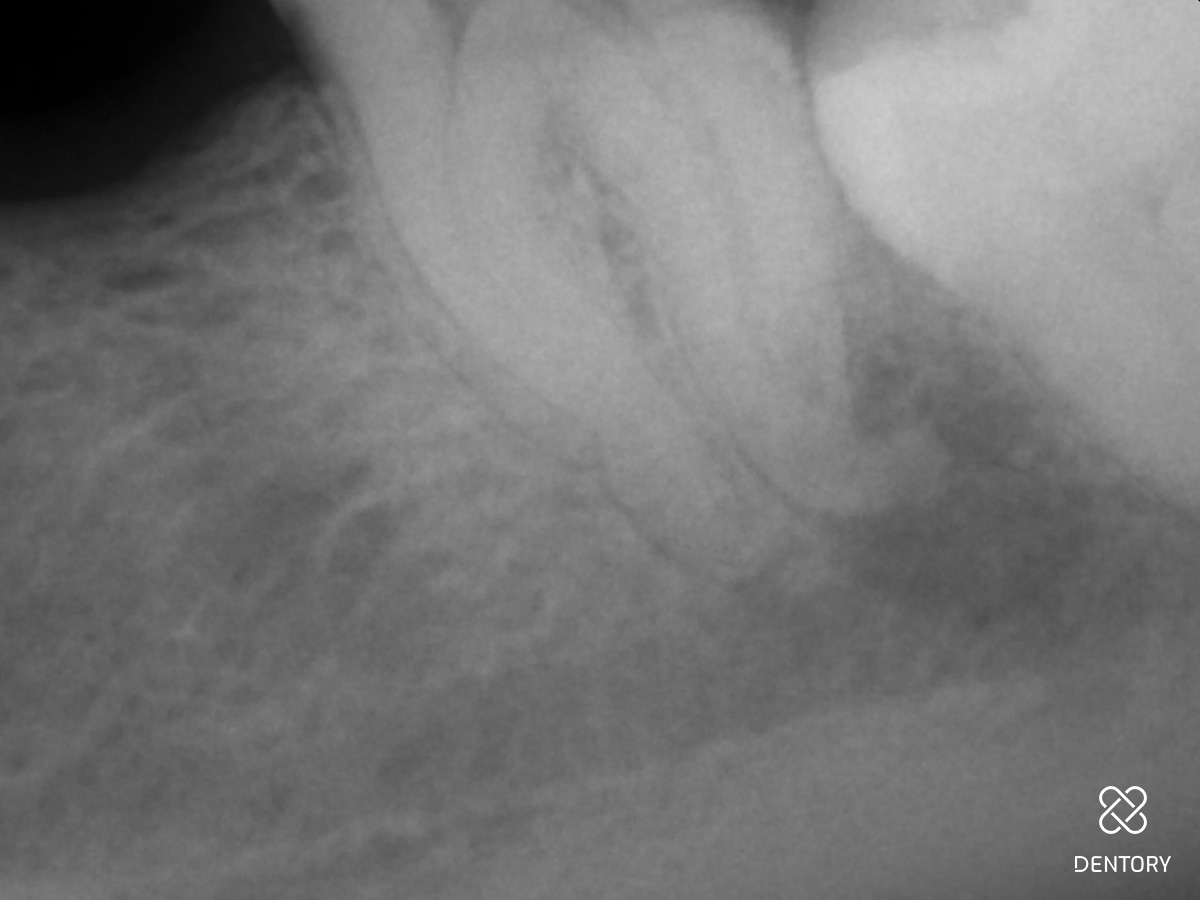

Abbildung 3

Aufbereitung des distalen Kanals: Es ist darauf zu achten, die Kontaktzeit im Kanal kurz zu halten sowie den Kanal abschnittsweise von koronal nach apikal zu bearbeiten. Zusätzlich verhindert eine regelmäßige Rekapitulation mit einer Handfeile bis zur endometrisch bestimmten Länge eine Verblockung des Kanals mit Debris.